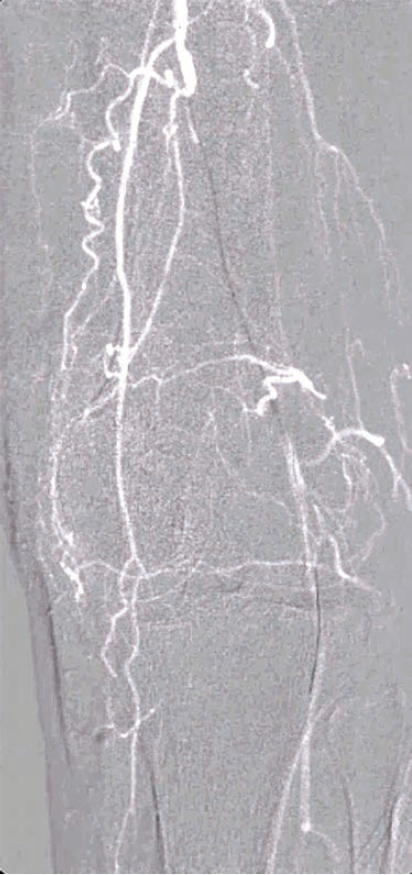

3. Digital Subtraction Angiography (DSA): The gold standard for angiographic imaging, particularly in the assessment of complex vascular anatomy. However, DSA requires multiple contrast injections, and exposes both patients and operators to substantial radiation, with about a 30-fold increase in radiation dose to the operating physician compared to low-dose fluoroscopy in some systems and procedures4 (when fluoro save is used, dose can be up to 100 times higher3).

The development of roadmap imaging has further refined the guidance of endovascular interventions. By generating a real-time, detailed overlay of vascular anatomy aligned to live fluoroscopy, roadmap imaging enables more precise and accurate navigation during these procedures, thereby reducing the risk of complications as well as improving patient outcomes.

Roadmap imaging represents a sophisticated blend of pre-acquired images (often from computed tomography [CT] angiography or DSA) with real-time fluoroscopy, providing a continuous overlay that allows for precise guidance throughout the procedure. The technology works by creating a “virtual road” overlaid onto live fluoroscopic images, facilitating catheter and device navigation.

Below-knee interventions are among the most challenging in endovascular procedures. The small vessel size, presence of extensive calcification, and complex collateral network make navigation difficult, especially in patients with chronic total occlusions (CTOs). Roadmap imaging provides several distinct benefits in the following situations:

2.Subintimal Access: In cases where intraluminal access is not possible, roadmap imaging can help guide operators into the subintimal space, increasing the chances of successful crossing in CTOs.